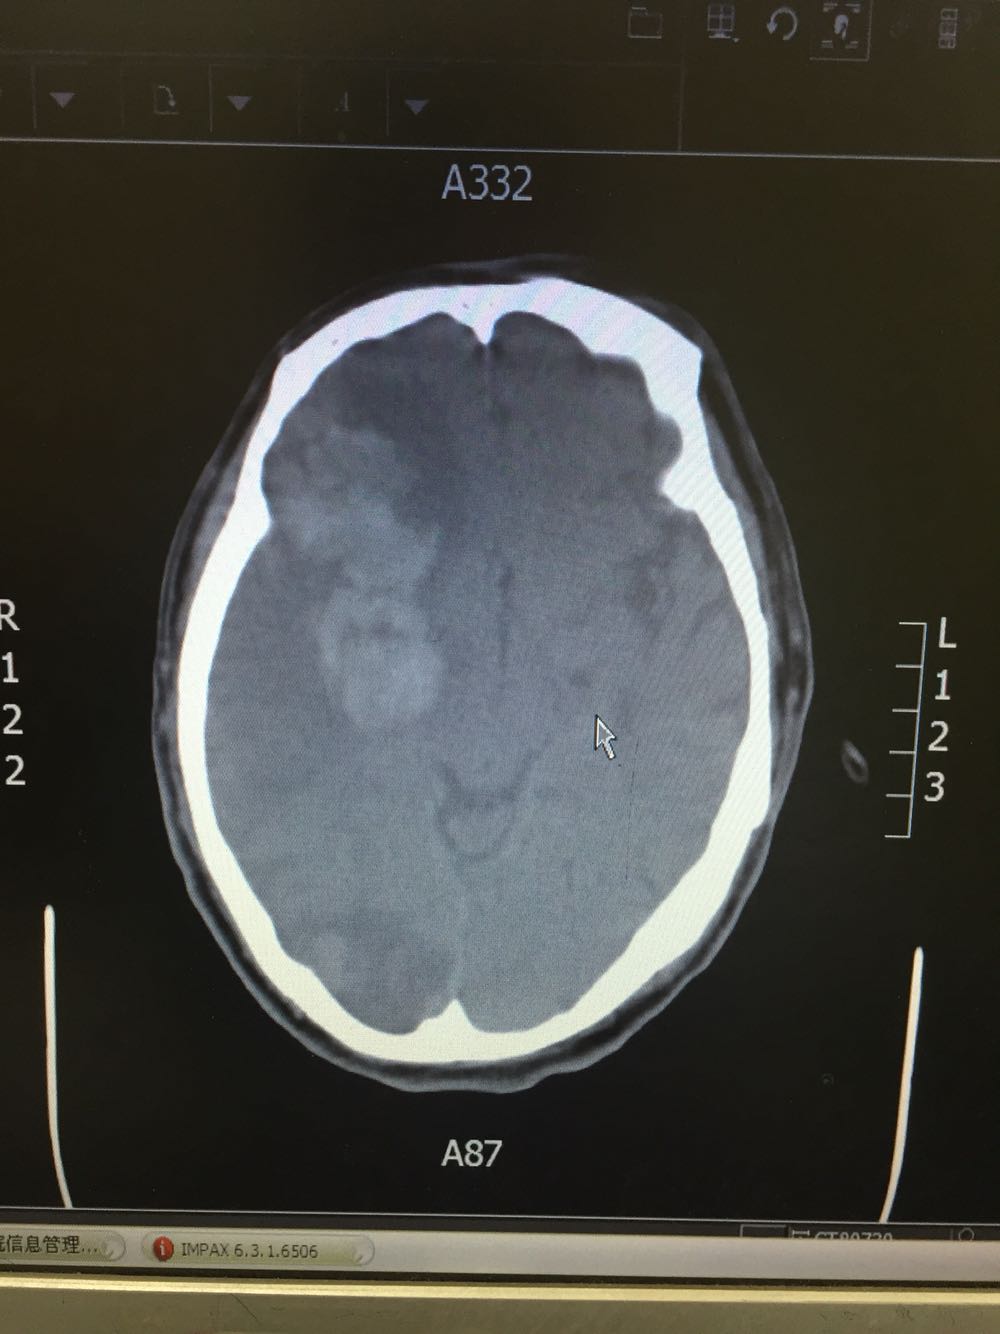

患者入院治疗后症状一度好转,左侧肢体肌力3级+,于入院后第二日病情突然加重,伴意识障碍,头DWI示:脑梗死伴脑出血 右侧大脑中动脉闭塞。停止当前治疗方案,脱水脑保护,营养神经对症治疗。入院后第5日复查头CT示:右侧大面积脑梗死,脑出血吸收期,伴左侧枕叶脑出血。患者左侧枕叶脑出血不好解释,能否是搬运及护理时外伤所致?